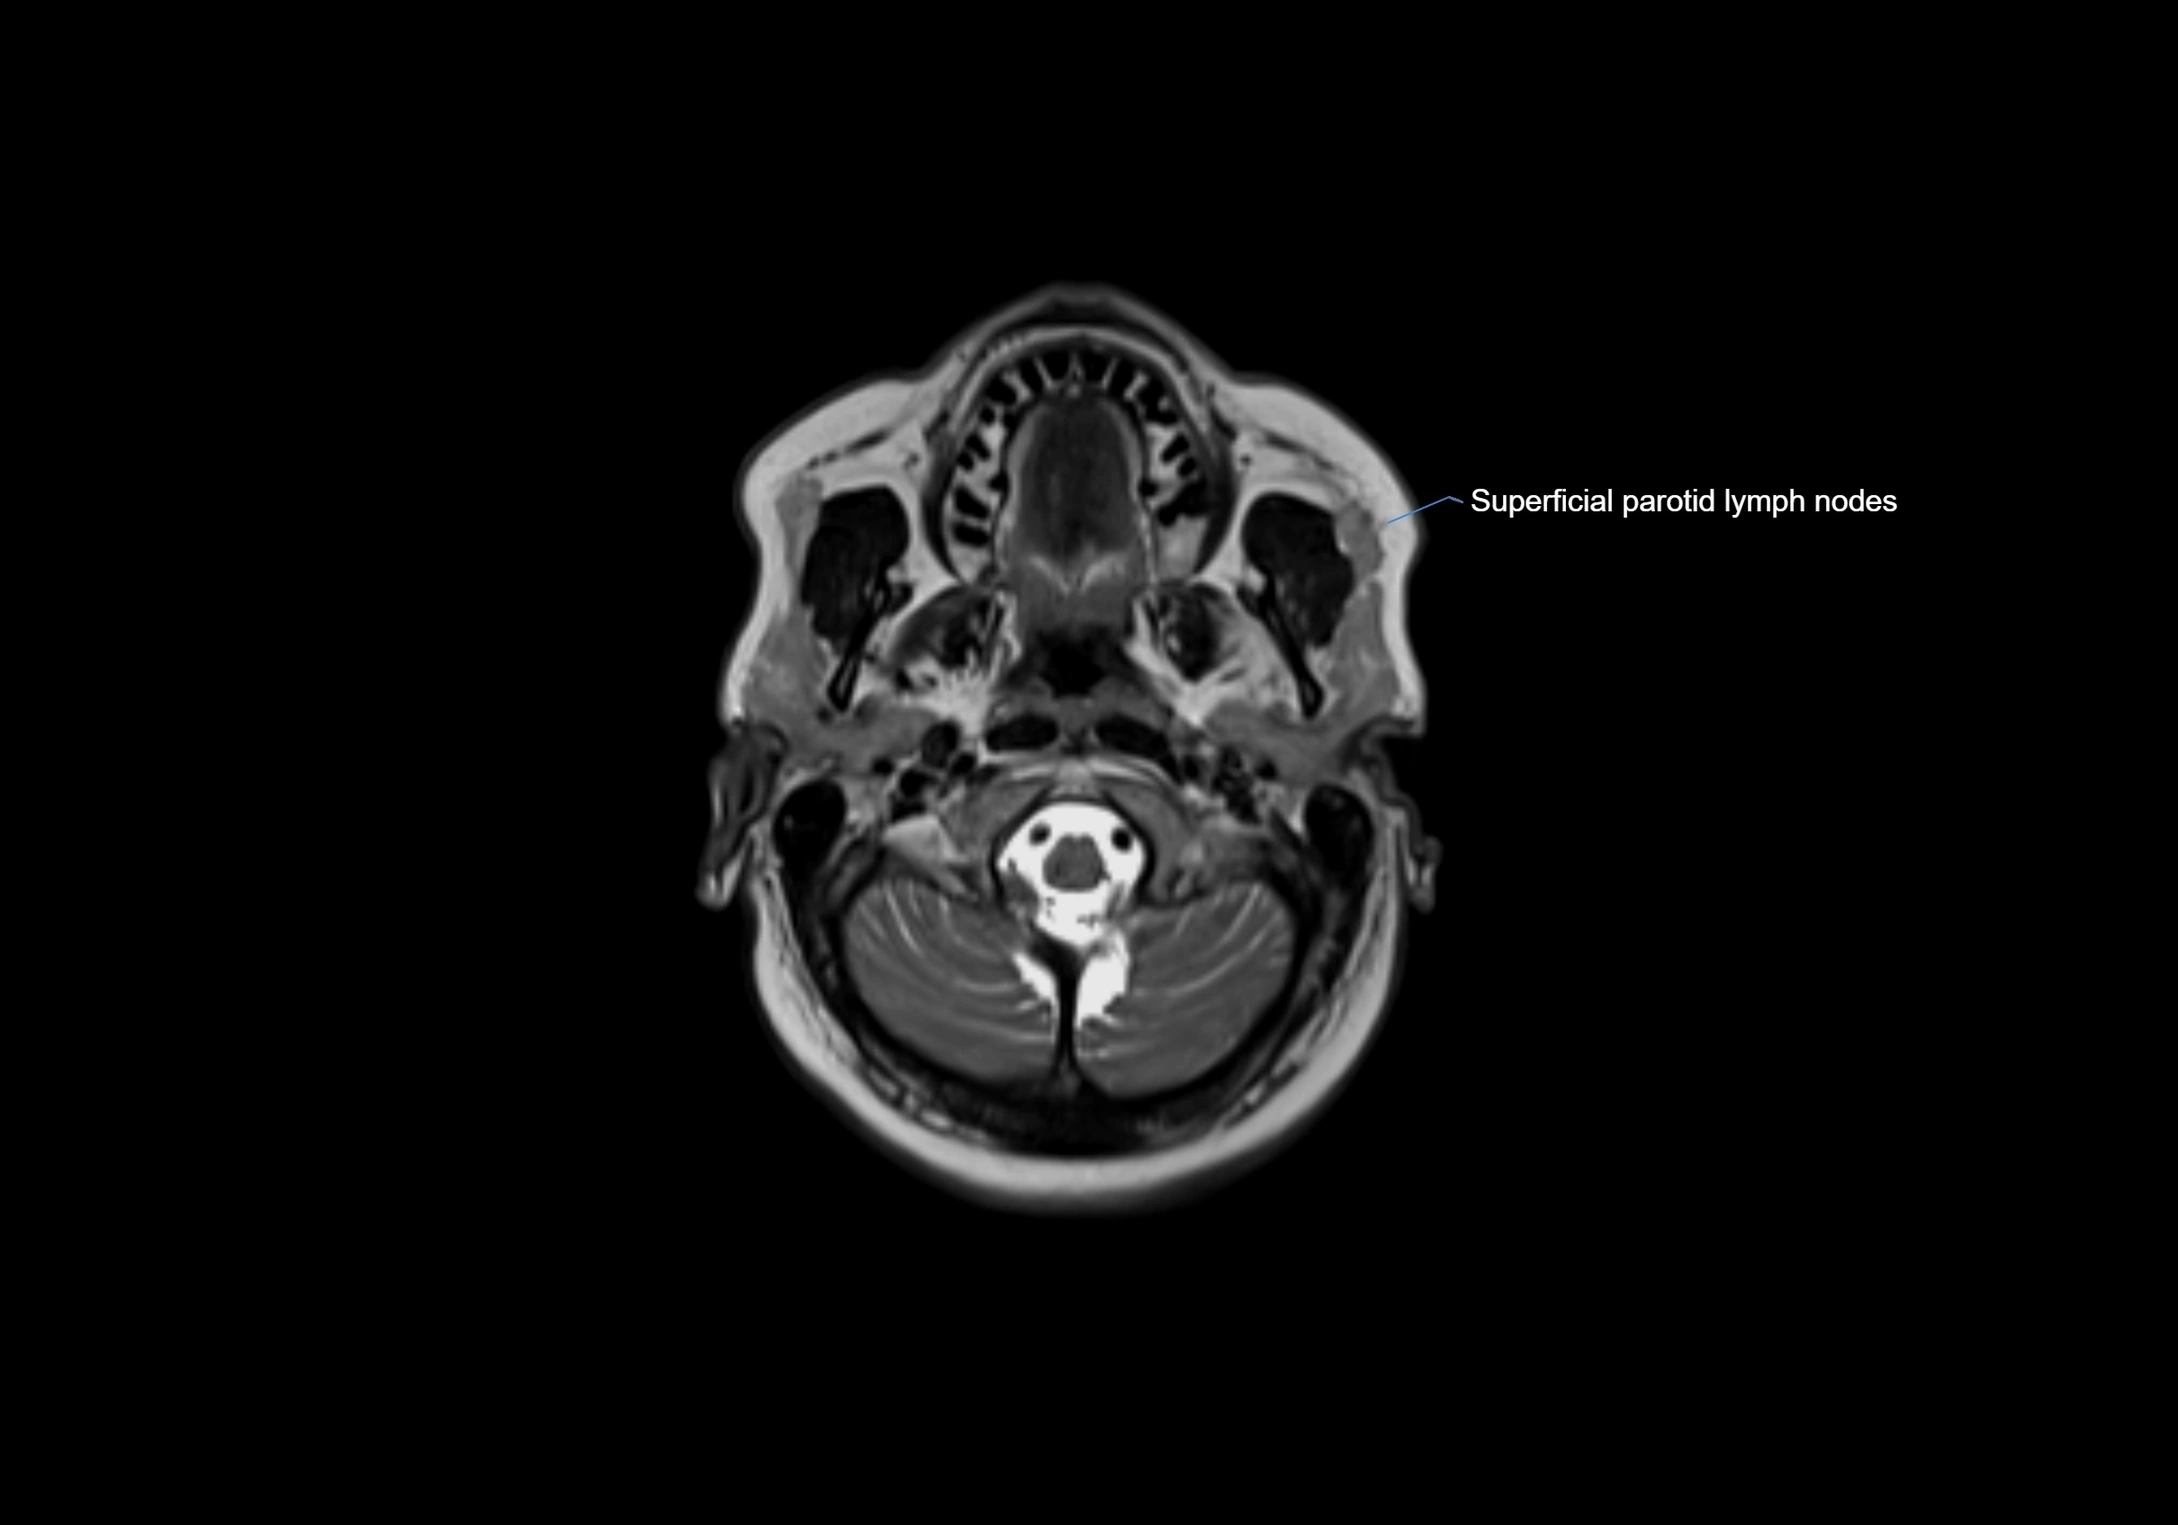

MRI Appearance

T1-weighted images:

• Normal accessory nodes appear as small, oval hypointense to intermediate signal structures within subcutaneous fat

• Surrounded by hyperintense fat, enhancing contrast for visualization

• Pathological nodes may appear enlarged or rounded, sometimes with cortical thickening

T2-weighted images:

• Nodes show intermediate signal, with surrounding fat bright

• Useful for detecting edema, inflammation, or infiltration

• Fatty hilum may appear slightly hyperintense relative to cortex

MRI images

image